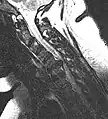

- Magnetic resonance imaging is the gold standard study for confirming a suspected LDH. With a diagnostic accuracy of 97%, it is the most sensitive study to visualize a herniated disc due to its significant ability in soft tissue visualization. MRI also has higher inter-observer reliability than other imaging modalities. It suggests disc herniation when it shows an increased T2-weighted signal at the posterior 10% of the disc. Degenerative disc diseases have shown a correlation with Modic type 1 changes. When evaluating for postoperative lumbar radiculopathies, the recommendation is that the MRI is performed with contrast unless otherwise contraindicated. MRI is more effective than CT in distinguishing inflammatory, malignant, or inflammatory etiologies of LDH. It is indicated relatively early in the course of evaluation (<8 weeks) when the patient presents with relative indications like significant pain, neurological motor deficits, and cauda equina syndrome. Diffusion tensor imaging is a type of MRI sequence used for detecting microstructural changes in the nerve root. It may be beneficial in understanding the changes that occur after herniated lumbar disc compresses a nerve root, and might help in differentiating the patients that need surgical intervention. In patients with a high suspicion of radiculopathy due to lumbar disc herniation, yet the MRI is equivocal or negative, nerve conduction studies are indicated.[44] T2-weighted images allow for clear visualization of protruded disc material in the spinal canal.

MRI scan of large herniation (on the right) of the disc between L4 and L5 vertebrae